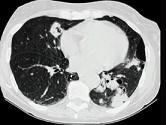

问题 68岁男性,咳嗽流涕1周入院,临床诊断为肺中叶综合征。支气管镜见多发结节状突起,从气管前壁伸入至右肺下叶支气管如图,影像检查如图。可能的诊断是 ( )

选项 A.肺结核 B.支气管肺癌 C.原发性气管支气管淀粉样变 D.肺炎 E.支气管内膜结核

答案 C